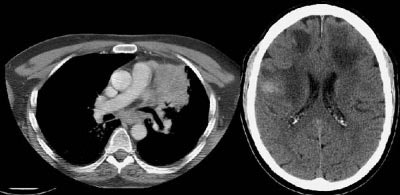

Example 2: This is an interesting case of a patient with non-small-cell lung cancer who complained of right shoulder pain. The bone scan demonstrates a bone lesion in the proximal right humerus (blue arrow) consistent with a metastasis. The scan also revealed linear uptake of tracer along the distal femurs and tibias bilaterally (black arrows). Uptake in the forearms was more irregular. A coned down plain film of the distal left femur demonstrated a solid periosteal reaction (white arrows). The findings are consistent with hypertrophic osteoarthropathy- a paraneoplastic condition seen in association with bronchogenic carcinoma.

NOTE: Click directly on the image to enlarge.